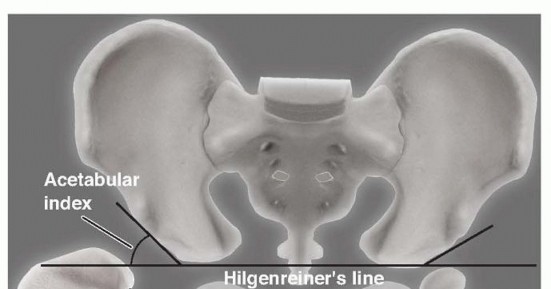

Pericapsular Osteotomies of Pemberton and Dega r DEFINITION The Pemberton 7 ( FIG 1 ) and Dega 1 , 2 ( FIG 2 …

Medial Approach for Open Reduction of a Developmentally Dislocated Hip DEFINITION Developmental dislocation o…

Innominate Osteotomy of Salter DEFINITION The Salter innominate osteotomy is commonly performed in conjunctio…